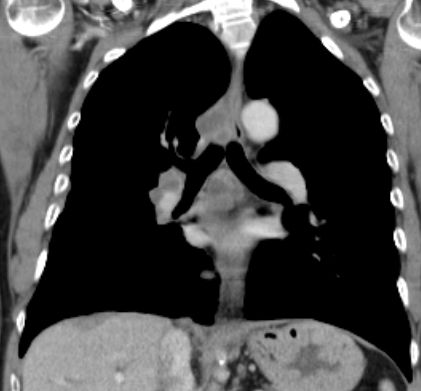

Primärtumor im linken Unterlappen. .